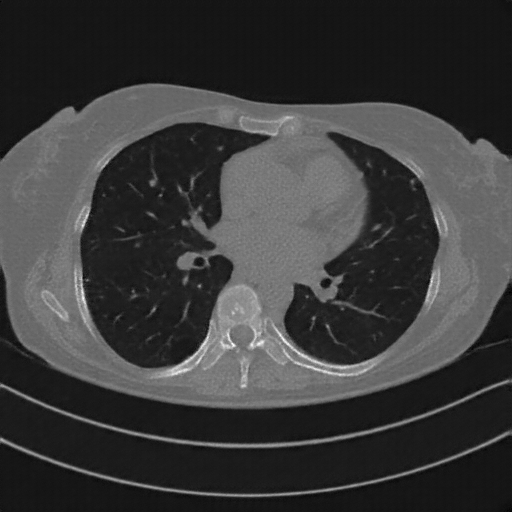

Original NATIVE CT scan (input)

No window - Raw intensity values

Original NATIVE CT scan (input)

Lung window (WL -600, WW 1500 → Low −1350, High +150)